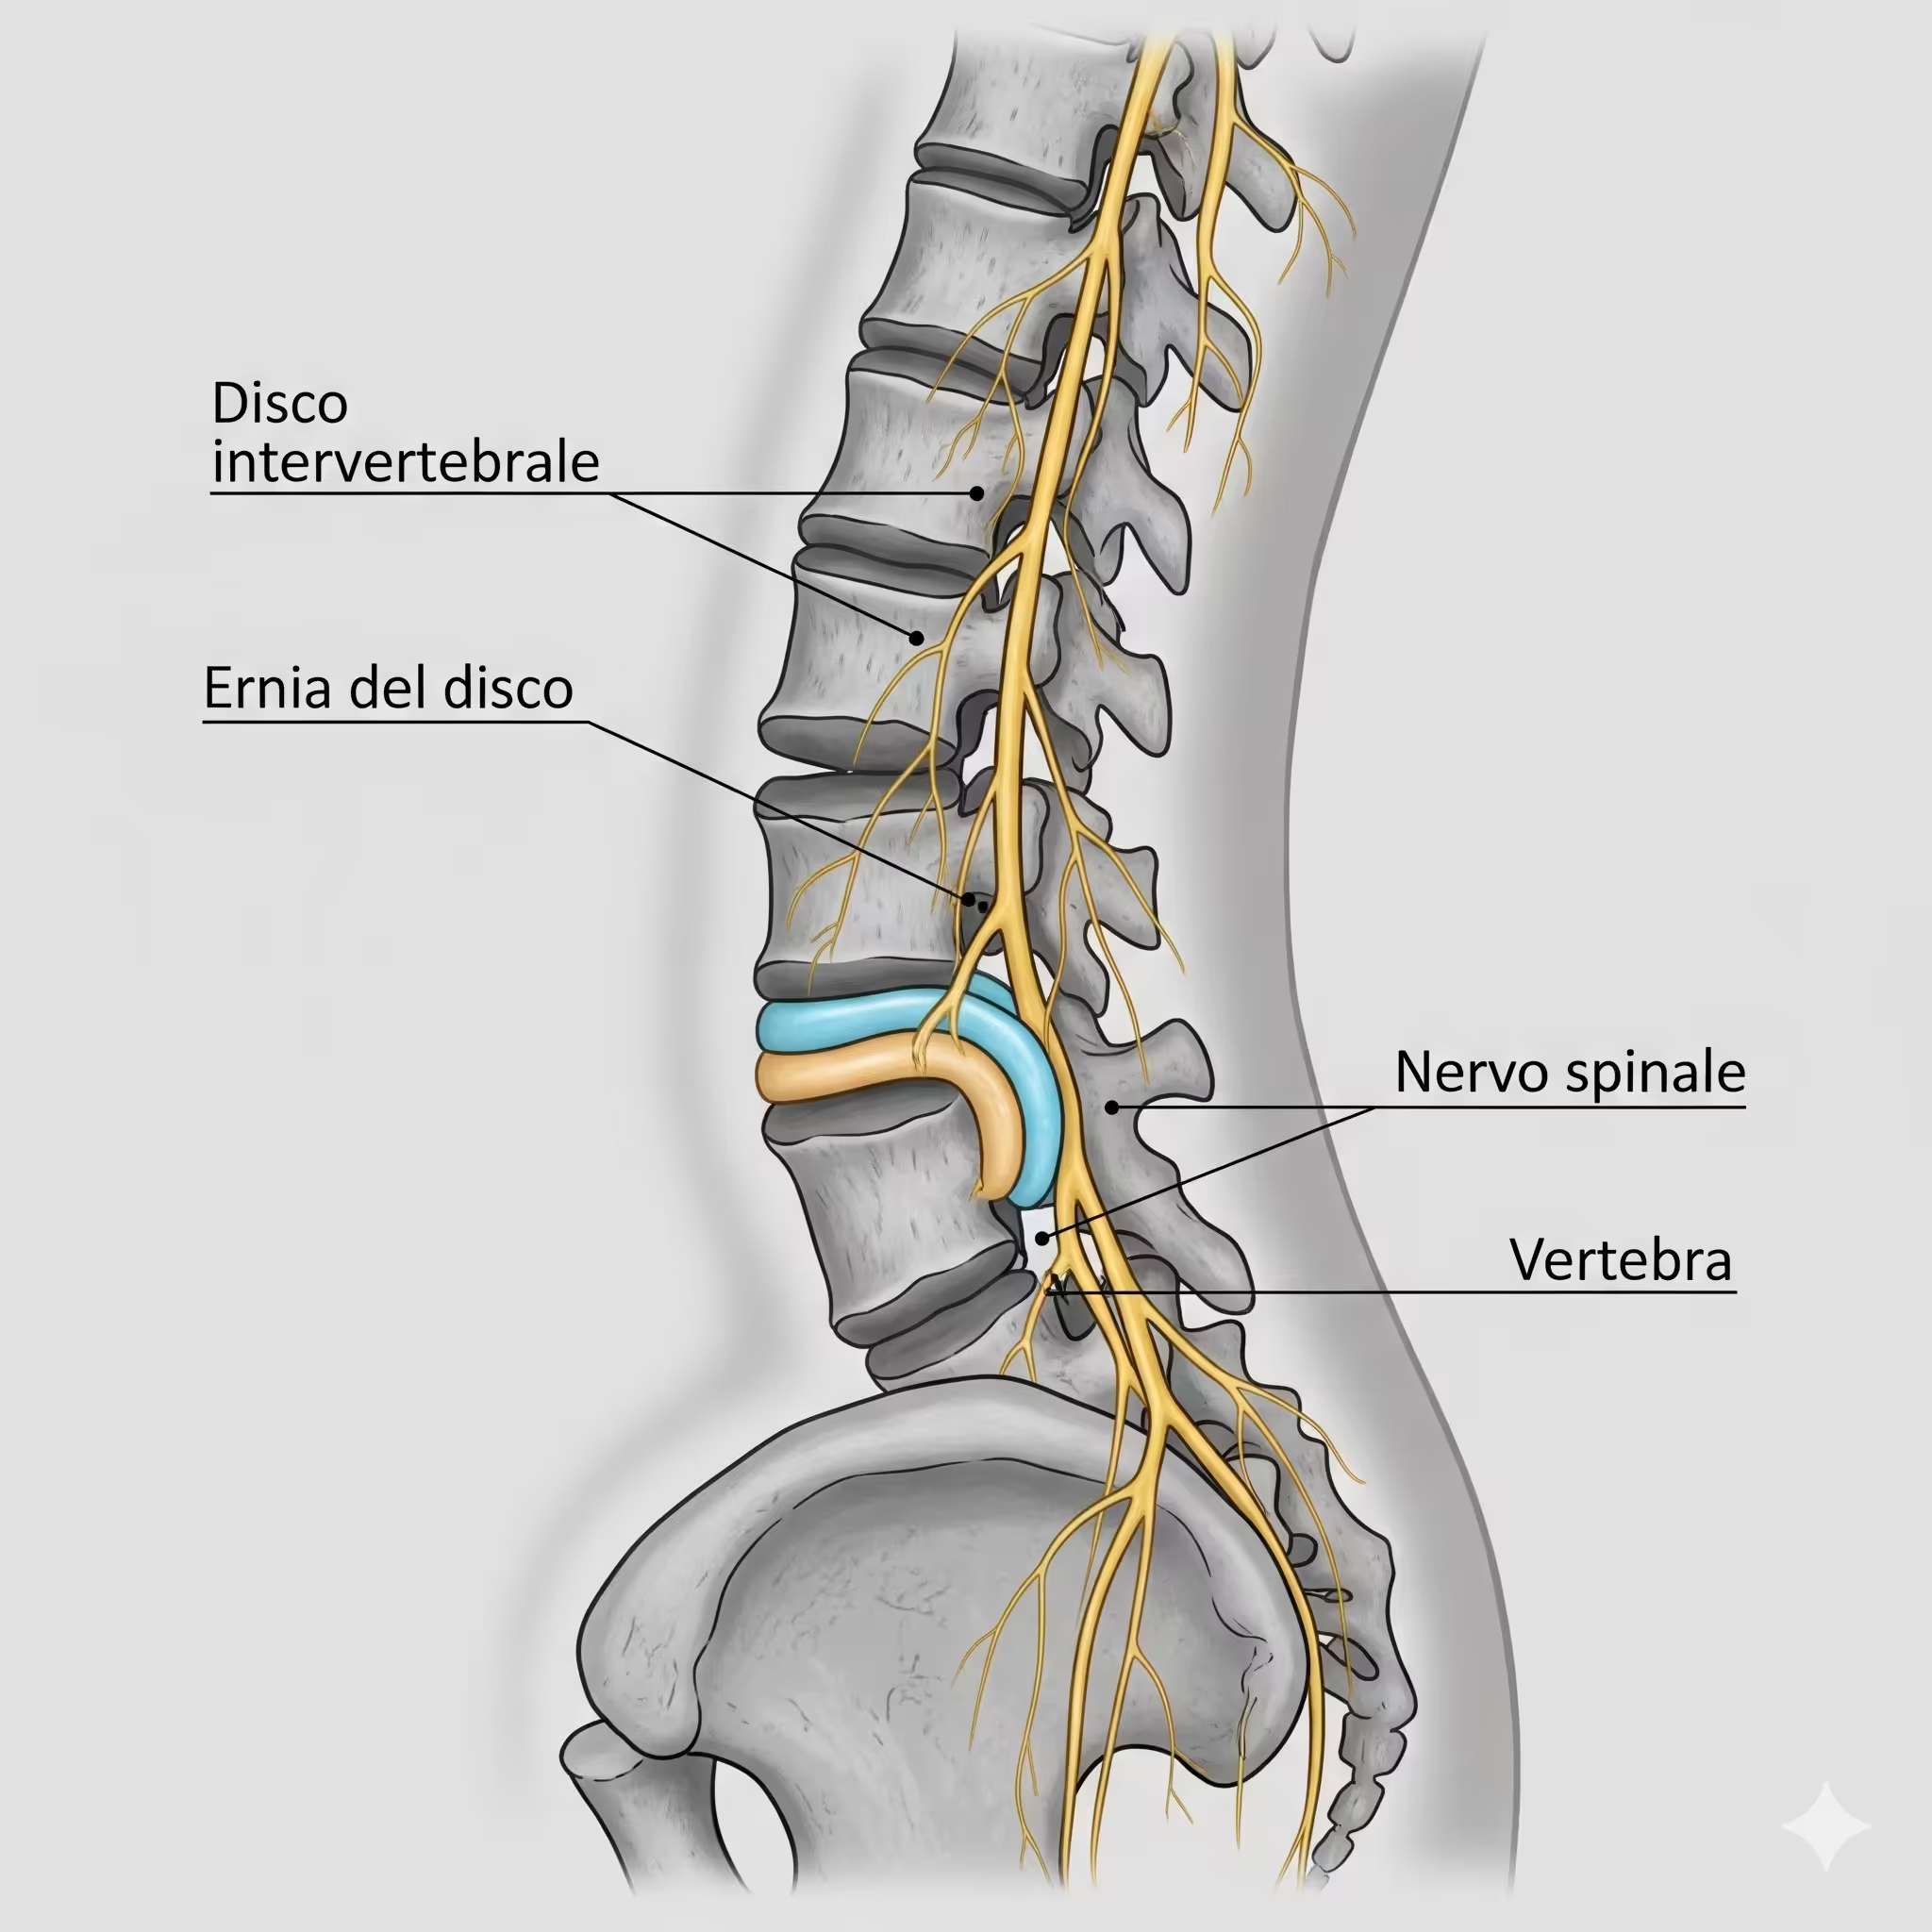

Dolori muscolo-scheletrici: Mal di schiena (lombalgia, sciatalgia), cervicalgia, dolori articolari (spalla, anca, ginocchio).

Problematiche posturali: Scoliosi, ipercifosi, dolori legati a posture scorrette.

Terapia Manuale: Tecniche specifiche come massoterapia decontratturante, mobilizzazioni articolari e manipolazioni vertebrali.

Rieducazione Funzionale e Motoria: Esercizi terapeutici mirati al recupero della forza, flessibilità, coordinazione ed equilibrio.

Ginnastica Posturale: Programmi individuali o di gruppo per correggere vizi posturali e prevenire dolori.

Ci focalizziamo sul recupero funzionale con rieducazione motoria personalizzata e mirata. Attraverso esercizi propriocettivi posturali, training di deambulazione e mobilizzazioni di colonna e articolazioni, i nostri specialisti lavorano per ripristinare il tuo benessere. Inoltre, eseguiamo massaggi decontratturanti e riflessogeni per darti sollievo e rilassamento.